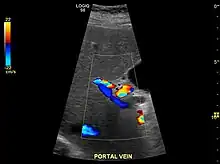

Ultrasound is routinely used in the evaluation of cirrhosis.[45] It may show a small and shrunken liver in advanced disease. On ultrasound, there is increased echogenicity with irregular appearing areas.[64] Other suggestive findings are an enlarged caudate lobe, liver surface nodularity[65] widening of the fissures and enlargement of the spleen.[66] An enlarged spleen, which normally measures less than 11–12 cm (4.3–4.7 in) in adults, may suggest underlying portal hypertension.[67] Ultrasound may also screen for hepatocellular carcinoma and portal hypertension.[45] This is done by assessing flow in the hepatic vein.[68] An increased portal vein pulsatility may be seen. However, this may be a sign of elevated right atrial pressure.[69] Portal vein pulsatility are usually measured by a pulsatility indices (PI).[68] A number above a certain values indicates cirrhosis (see table below).